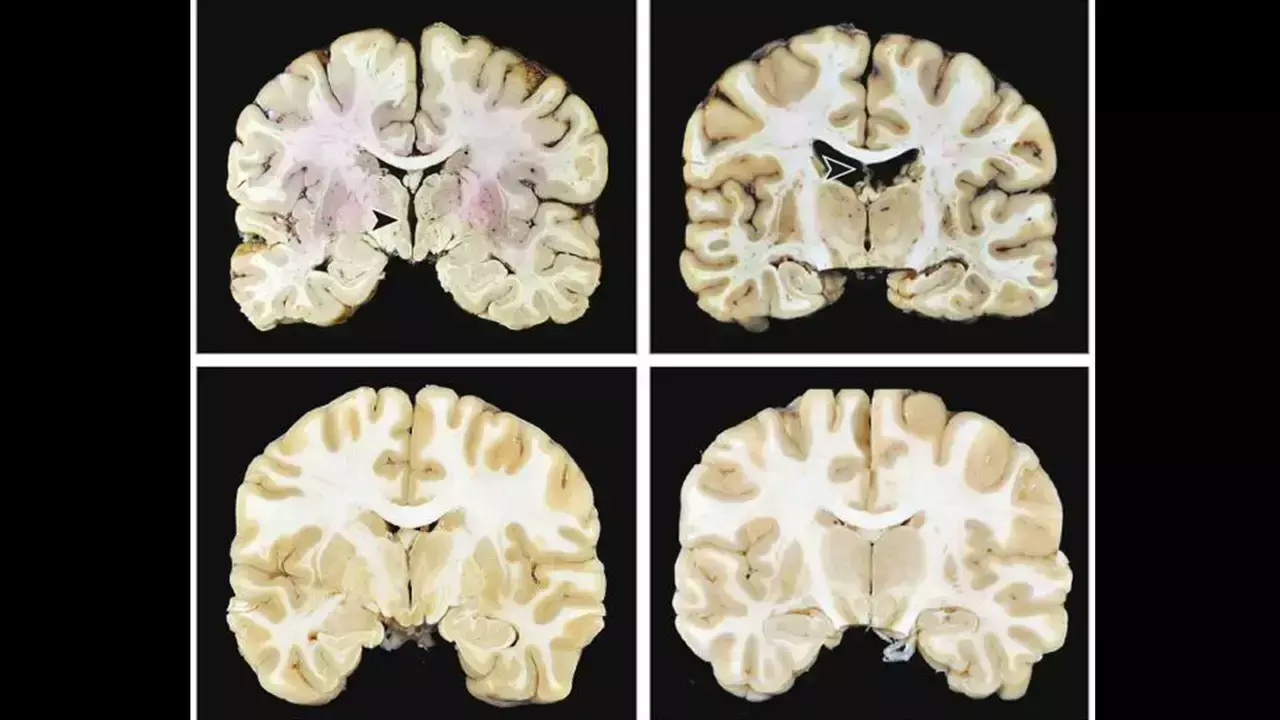

Researchers have found in a large autopsy study of brain donors that without other progressive neurodegenerative diseases, stage III and IV chronic traumatic encephalopathy were associated with significantly higher odds of dementia. In contrast, early-stage (I–II) chronic traumatic encephalopathy showed no association with cognitive symptoms or dementia, indicating that dementia risk rises with advanced chronic traumatic encephalopathy pathology.

This studyexamined the independent contribution of chronic traumatic encephalopathy (CTE) neuropathology to symptoms. The sample included 614 brain donors with (n = 366) and without (n = 248) autopsy-confirmed chronic traumatic encephalopathy. Brain donors with other major neurodegenerative disease diagnoses were excluded. Informants completed cognitive and neuropsychiatric measures. Dementia was determined during diagnostic consensus conferences.

chronic traumatic encephalopathy stage IV (of IV) was associated with 4.48 (95% confidence interval [CI] = 1.97–10.90) increased odds of having dementia. chronic traumatic encephalopathy stage III had an odds ratio of 2.12 (95% CI = 1.91–3.77). A higher chronic traumatic encephalopathy stage was associated with greater informant-reported cognitive symptoms (p < 0.01).

There were no associations with mood/behavioural scales. Chronic traumatic encephalopathy stage III/IV neuropathology was associated with dementia and cognitive symptoms: those with stage IV were 4.5 times more likely to have dementia than those without chronic traumatic encephalopathy. It is uncertain if low-stage chronic traumatic encephalopathy clinically manifests, and mood/behavioural symptoms likely have multifactorial causes and/or a fluctuating course.

Stage III and IV chronic traumatic encephalopathy (CTE) are independently associated with increased odds of having dementia.